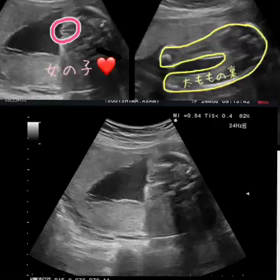

予定日まであと98日

2017年6月16日